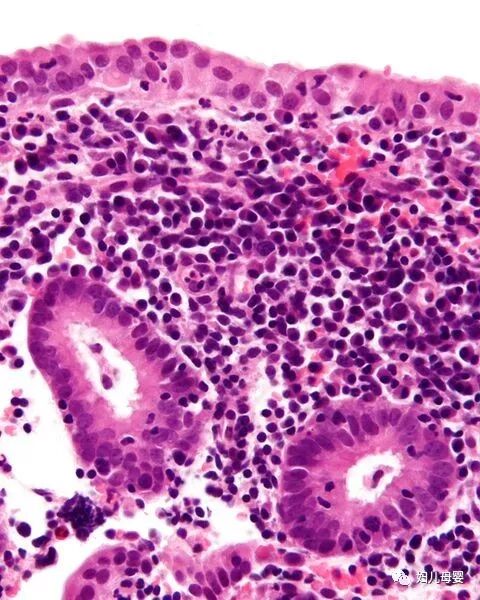

#国民医生说##健闻登顶计划##微博热点优质创作计划# 畸胎瘤是怀了“怪胎”吗?和胚胎发育有关吗?畸胎瘤并不是怀了 “怪胎”,它本质上是一种生殖细胞肿瘤,和正常胚胎发育没有直接关联,这是一个极易引发误解的医学概念。从病理本质来看,畸胎瘤是由胚胎时期的生殖细胞异常分化形成的肿瘤,而非真正的 “胎儿”。生殖细胞本应分化为人体的各类组织器官,但在发育过程中,部分细胞脱离了正常的分化轨道,在卵巢、睾丸等部位异常增殖,最终形成包含多种组织成分的肿瘤 —— 它可能含有毛发、牙齿、骨骼、油脂甚至少量神经组织,这些只是分化紊乱的人体组织,并非完整的胚胎或 “怪胎”。关于和胚胎发育的关联,需要区分两个层面:一方面,畸胎瘤的起源确实和胚胎阶段的生殖细胞有关,其发病根源是胚胎期生殖细胞的分化异常;但另一方面,它和母体的正常妊娠、胚胎孕育没有任何关系,既不是母体怀孕时形成的 “异常胎儿”,也不会因为怀孕而诱发或加重,未婚未育人群也可能患上畸胎瘤。另外,畸胎瘤多数为良性(成熟畸胎瘤),少数为恶性(未成熟畸胎瘤),良性畸胎瘤通过手术切除即可治愈,恶性类型则需结合病理分级进行后续治疗,总体预后相对较好,无需因 “畸胎” 的名称产生过度恐慌。